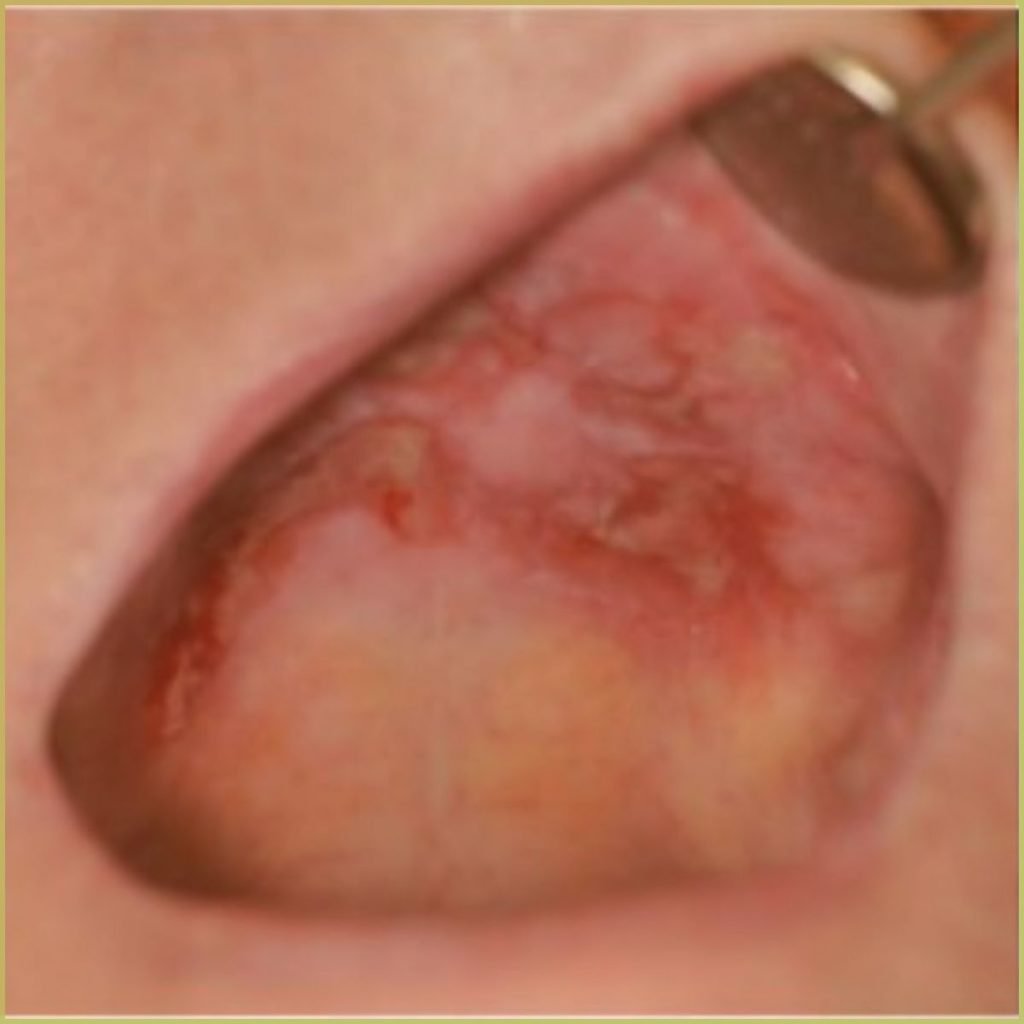

LICHEN PLANUS

Lichen Planus (Wickham striae) is a chronic inflammatory autoimmune disease that can affect the skin, nails, hair and mucous membranes. Oral lichen planus affects 3-4% of the population and is typically characterized by the presence of distinct reticular white lesions. The cause is not well understood but thought to involve the targeting of basal keratinocytes by activated T Cells. Clinical variations include erosive/ulcerative, papular, plaque-like, atrophic and bullous lesions. Multiple types may be found in the same patient and even in the same lesion. The common clinical presentation includes:

- Asymptomatic reticular lace-like patterns is the most common appearance.

- Most often located on the buccal mucosa, then tongue, gingiva and lips.

- Bilateral, often symmetrical distribution.

- Erosive or atrophic pattern can present with symptoms (pain or burning)

- Extra-oral lichen planus may accompany oral presentation (planar (flat-topped), purple, polygonal, pruritic, papules, and plaques).

- Higher incidence in white females and more likely in the fourth to eighth decade.

Diagnosis is based on the lesion history, clinical presentation and microscopic findings, which may include:

- Hyperkeratosis.

- Liquefactive degeneration of the basal layer of the epithelium.

- Presence of Civatte bodies (apoptotic keratinocytes).

- Band-like appearance of inflammatory infiltrate (lymphocytes) in the mucous membranes beneath the epithelium.

- No epithelial dysplasia.

- Saw tooth rete ridges.

Your differential diagnosis should include:

- Lichenoid drug reactions.

- Lupus erythematosus.

- Mucous membrane pemphigoid.

- Erythema multiforme.

- Contact stomatitis.

Reticular oral lichen planus does not require treatment and does not progress to a more serious disease. For symptomatic lesions, immune-suppressing agents can be utilized. Treatment options include:

- Topical corticosteroids for mild to moderate cases.

- Systemic prednisone for more severe cases.

- Topical tacrolimus ointment.

Though treatment does not provide a cure, long term control can be established. The prognosis is generally good with very rare malignant transformation.